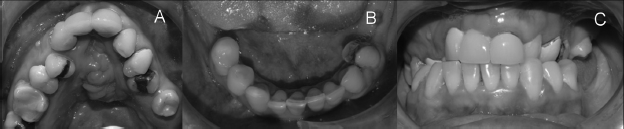

Paciente de sexo femenino, de 10 años y 8 meses de edad, con una apariencia de mayor edad, que consulta para evaluación y posibilidad de tratamiento rehabilitador en sector anterior. Presenta diagnóstico de fisura labiopalatina bilateral, con ausencia de premaxila y visible comunicación buconasal en dicha zona. En el examen extraoral se observa compromiso y deformación del ala nasal y punta de la nariz, y labio superior corto con secuela cicatricial. Presenta una clase III esqueletal y severa mordida invertida en el sector anterior. Existe compromiso de la sonrisa debido a la ausencia completa de las piezas dentarias anterosuperiores, además de gingivitis y múltiples lesiones de caries. A nivel social, la paciente dejó sus estudios básicos en el colegio debido al rechazo de los compañeros por su apariencia y dificultad en el habla a causa de las secuelas de la fisura (fig. 1).

Paciente de sexo femenino, de 37 años de edad, derivada para evaluación en ortodoncia con diagnóstico de fisura labiopalatina bilateral con una considerable fístula residual en reborde. En el examen extraoral se observa una clase III esqueletal, con falta de desarrollo del tercio medio facial, compromiso del ala nasal y labio superior, con buen resultado en la cicatriz. A nivel intraoral presenta hipoplasia del maxilar, mordida cruzada bilateral, con oclusión vis a vis anterior, línea media desviada 3 mm hacia la derecha y ausencia de piezas dentarias 1.8, 2.2, 2.6, 2.7, 3.8, 3.7, 3.6, 3.4, 4.6, 4.7 y 4.8 (fig. 3).

A. Oclusal superior (arcada con forma triangular). B. Oclusal inferior. C. Arcadas en oclusión (mordida cruzada bilateral severa)